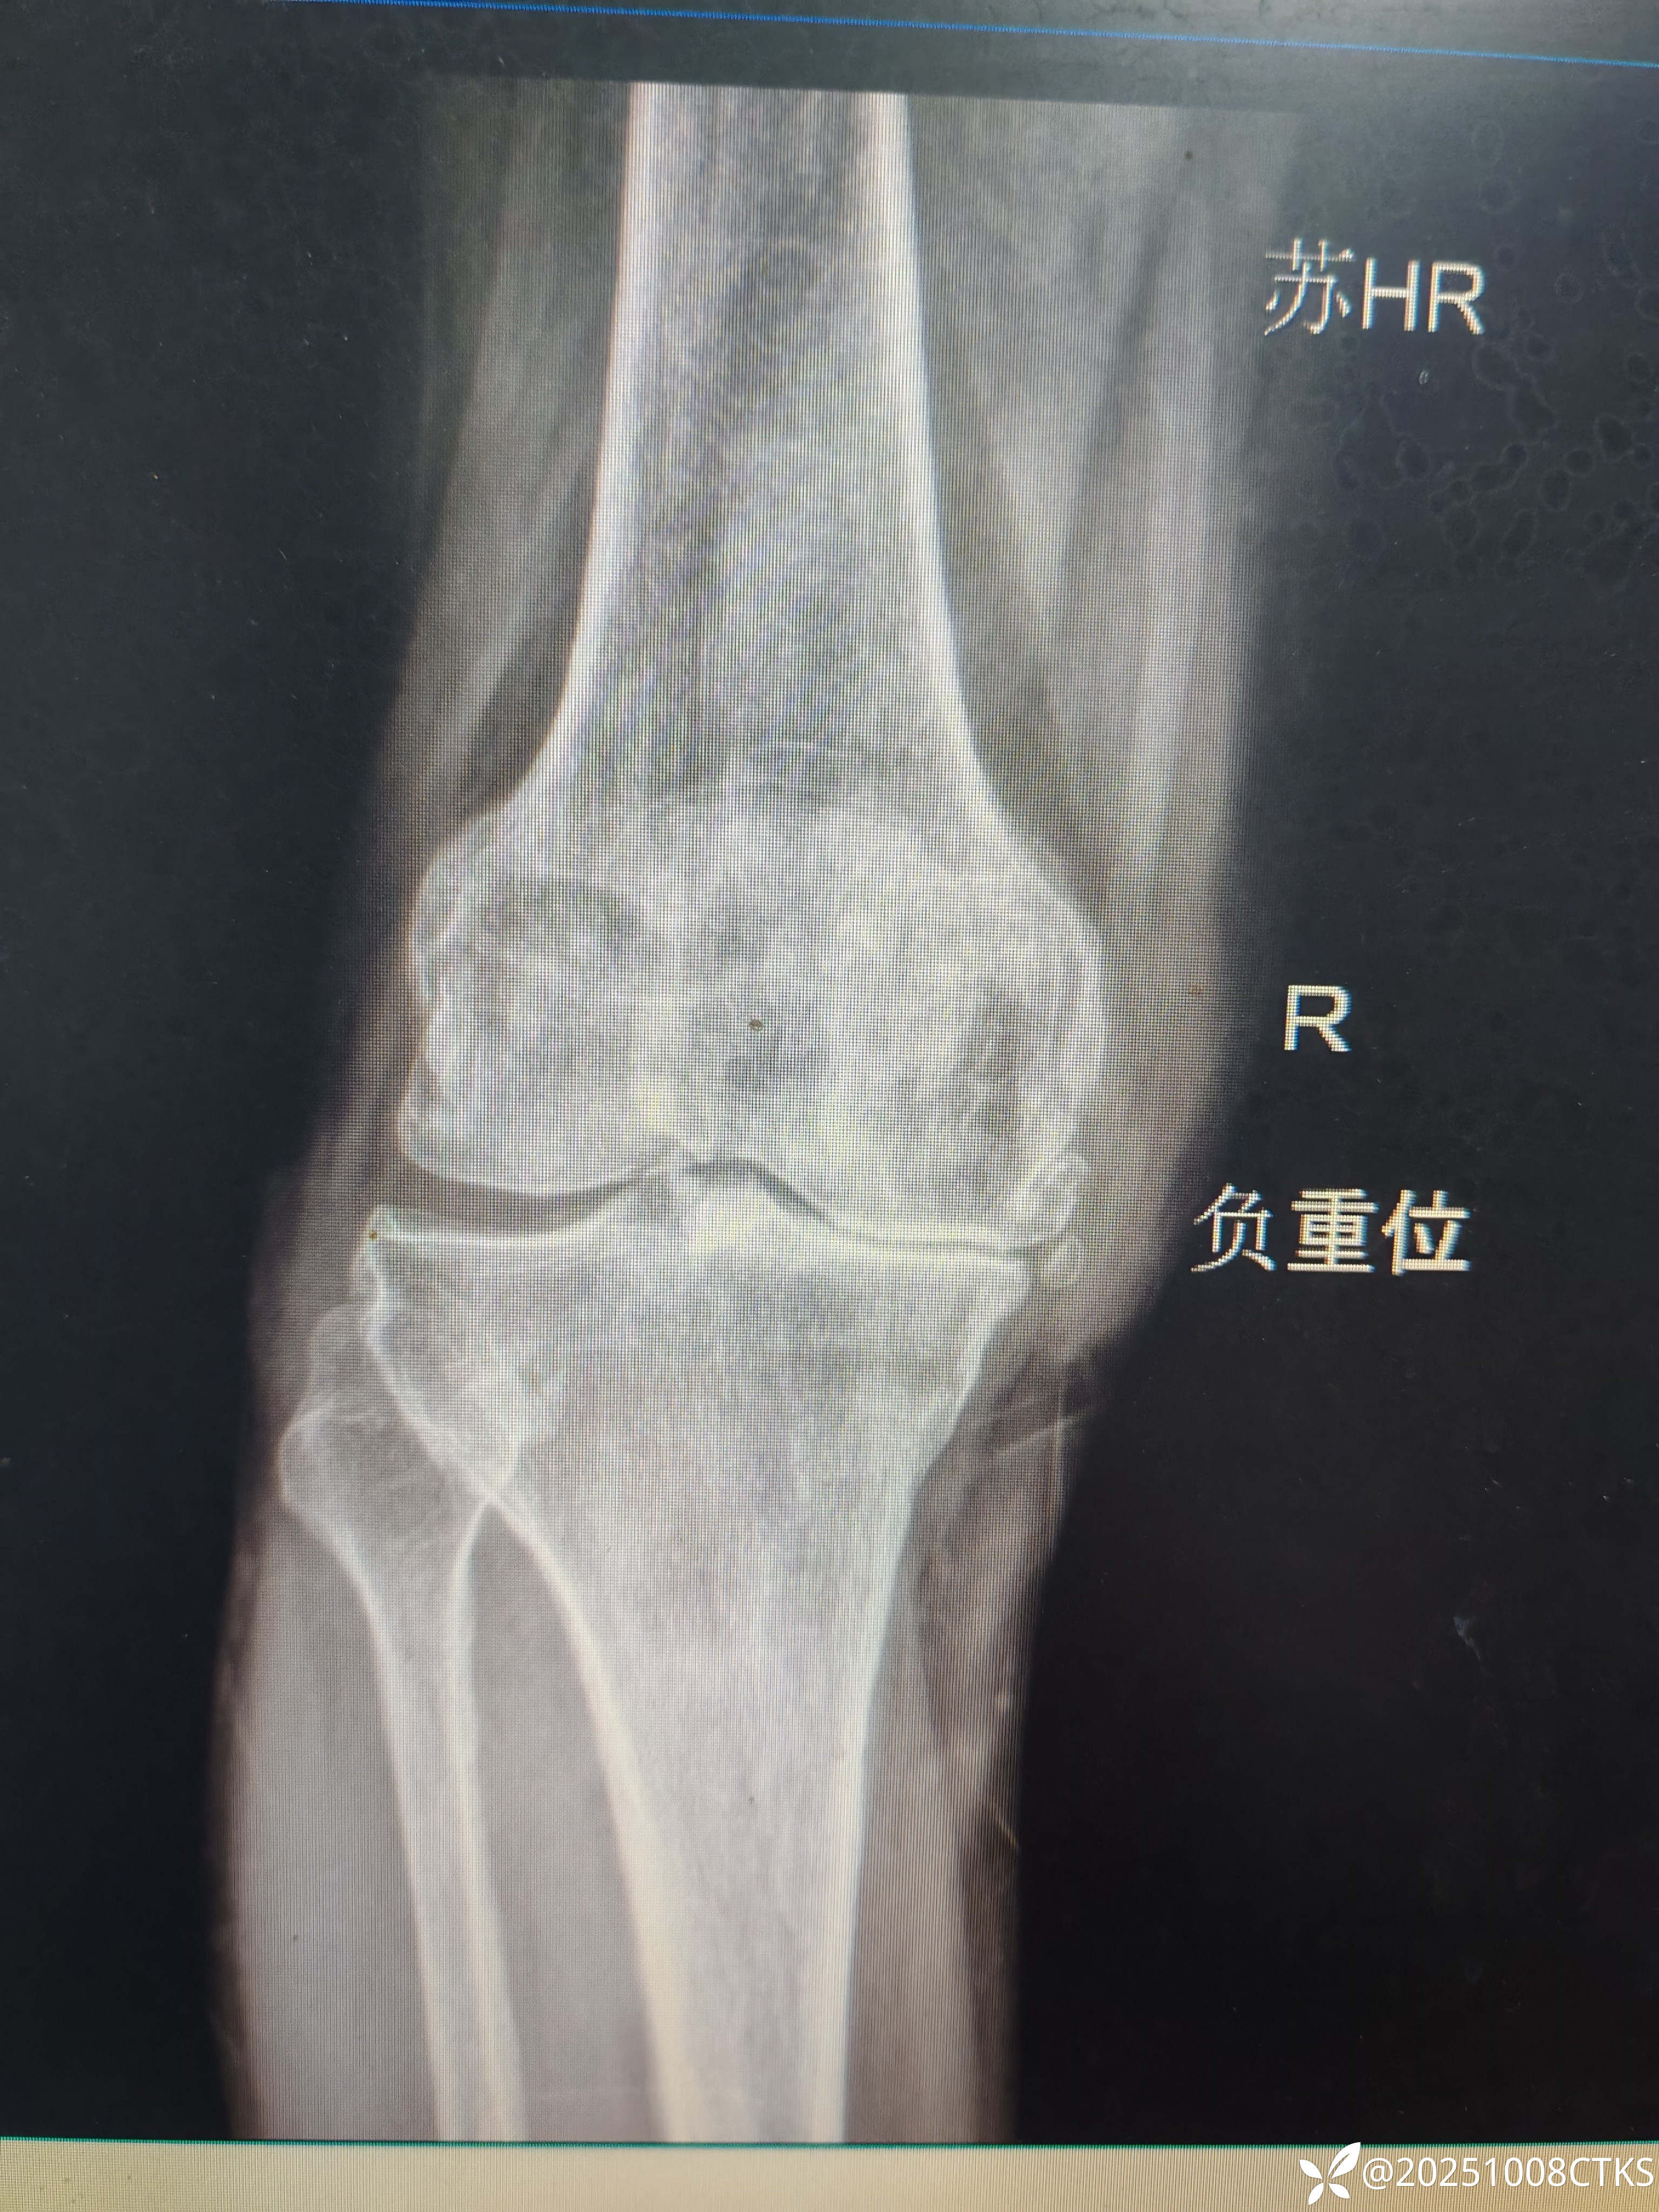

患者,男,69岁,膝关节疼痛十年余,外院建议膝关节关节置换,患者想保守治疗

膝关节退行性变,保守治疗方案有没有好的保守治疗方案,各位老师可以指导一下。